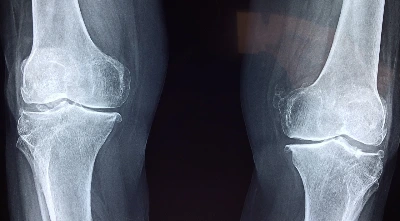

39살에는 몰랐지만, 40이 되는 순간 신기하게 달라지네요. 계단 내려가거나, 뛰어야 할 일이 생겨 달리기를 하다보면, 갑자기 무릎이 아파옵니다. 엄마가 돌아가시기 전에 계속 무릎이 시리다고 했고, 열 살 많은 선배도 무릎이 아파서 잘 못걸었다는 이야기를 들은 적이 있습니다. 이제 나도 무릎이 아파오는구나 생각하니, 마음은 불편하지만, 조금 더 체력관리를 해야겠다 생각하게 됩니다.